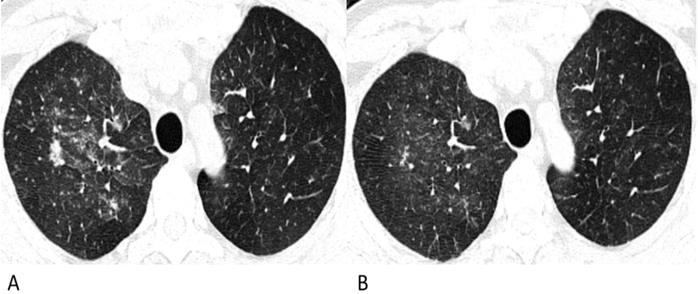

Figure 3

Follow-up chest CT images of lymphoma-associated pneumonia. A 49-year-old man was diagnosed with diffuse large B-cell lymphoma, and received chemotherapy with rituximab before the chest CT. He had a fever during the chemotherapy, but had no epidemiological history of COVID-19. (A) On the initial chest CT, diffuse patchy GGOs with several solid nodules are shown in both upper lobes. (B) After antibiotic and symptomatic treatment, the lesions in the follow-up CT are diminished, and the density decrease.

However, for lymphoma patients with pneumonia, solid nodules occupied 77% in nodular lesions, while for COVID-19 patients, GGO and mixed GGO nodules occupied 83% (p = 0.002). Notably, compared with the lesions of COVID-19 patients which were relatively limited or confined, the lesions of lymphoma patients were much more diffuse in the lung, like the “diffuse mist” (p < 0.001) (Fig. 1). This may be a critical characteristic in identifying pneumonia associated with lymphoma from that associated with COVID-19. Furthermore, air bronchograms were seen less frequently in lymphoma patients with pneumonia than in COVID-19 patients (5% vs. 45%, p < 0.001). Additionally, no halo sign or reversed halo sign was observed in lymphoma patients with pneumonia. After antibiotic and symptomatic treatment, the patchy lesions on the follow-up CT of the lymphoma patient decreased (Fig. 3); therefore, the patient was able to tolerate continuous chemotherapy.